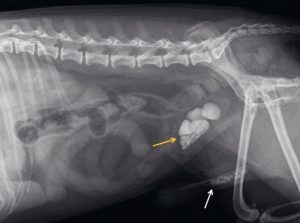

Naast het lichamelijk onderzoek om ook te beoordelen of er geen schade is in belangrijke organen, zal het nodig zijn om aanvullend röntgenfoto’s te maken.

Elk dier kan een bot breken. Vaak ten gevolge van een ongeluk, denk hierbij aan een val of botsing in het verkeer. Naast een botbreuk, kan er nog meer schade in het lichaam zijn. Heel belangrijk is dat het dier volledig onderzocht wordt, omdat er vaak nog meer schade inwendig kan zijn. Voorbeelden zijn: een klaplong, bloeding elders in het lichaam of bijvoorbeeld een hersenschudding.

In veel gevallen is operatie de beste behandeling. De dierenarts zal de behandelopties, voor- en nadelen, herstelkansen en kosten met u bespreken. Afhankelijk van het type breuk en andere beschadigingen in het lichaam is de prognose gelukkig vaak wel gunstig.